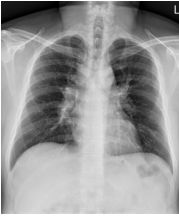

3. This 72-year-old diabetic man was taken to ER for productive cough for 10 days, and rapid progressive dyspnea for 2 days. He also had fever and chill for a week.